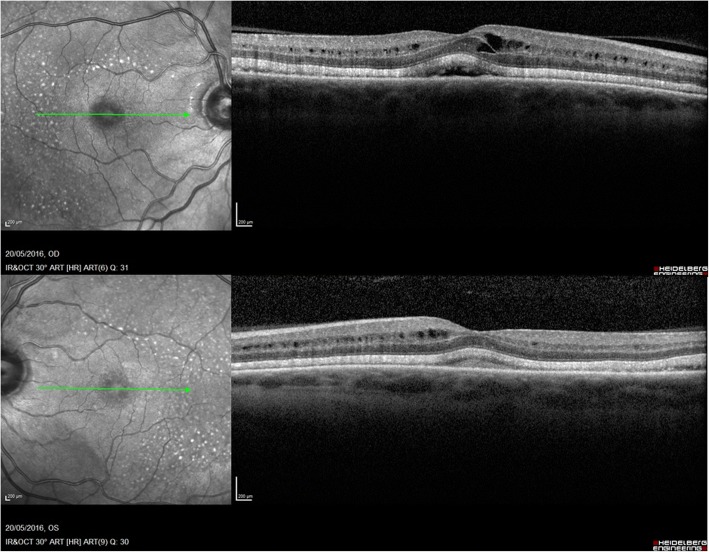

Fig. 5.

Change in OCT appearance in both eyes over 6 months: Resolution of cystoid macular edema in perifoveal region, reduction in the intra-retinal and sub-retinal fluid. The ellipsoid zone thickening and subretinal granular deposits remained unchanged in right (a) and left (b) eye

His chemotherapeutic drugs, Dabrafenib and Trametinib were withheld for 3 weeks. He noticed subjective improvement in symptoms with clearing of dark patches in his vision within 10 days. His vision, fundus and OCT appearances were unchanged. He was recommenced on reduced dose of Dabrafinib (100 mg) BD and Trametinib (1 mg) OD after 3 weeks to prevent melanoma relapse. He remained visually asymptomatic and clinically unchanged on this dose for 6 months. Over time, the cystoid macular edema resolved in the perifoveal region with reduction in the intra-retinal and sub-retinal fluid. The ellipsoid zone thickening and subretinal deposits remained unchanged (Fig. 5). Unfortunately, the patient’s melanoma progressed and he was awaiting further chemotherapy with Pembroluzimab.